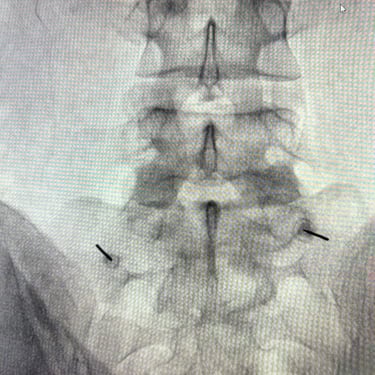

La discopatía lumbar y la espondiloartrosis forman parte del proceso degenerativo de la columna vertebral y pueden generar dolor lumbar persistente, irradiación hacia miembros inferiores y limitación funcional. Diversos estudios clínicos han demostrado que el bloqueo lumbar selectivo es una herramienta diagnóstica y terapéutica útil en estos pacientes. El procedimiento consiste en la infiltración guiada por fluoroscopía o ecografía de anestésicos locales y corticoides cerca de la raíz nerviosa o articulación facetaria comprometida. Esta técnica permite confirmar la fuente del dolor y disminuir la inflamación neural. En pacientes seleccionados, puede mejorar significativamente la calidad de vida y retrasar o evitar tratamientos quirúrgicos.